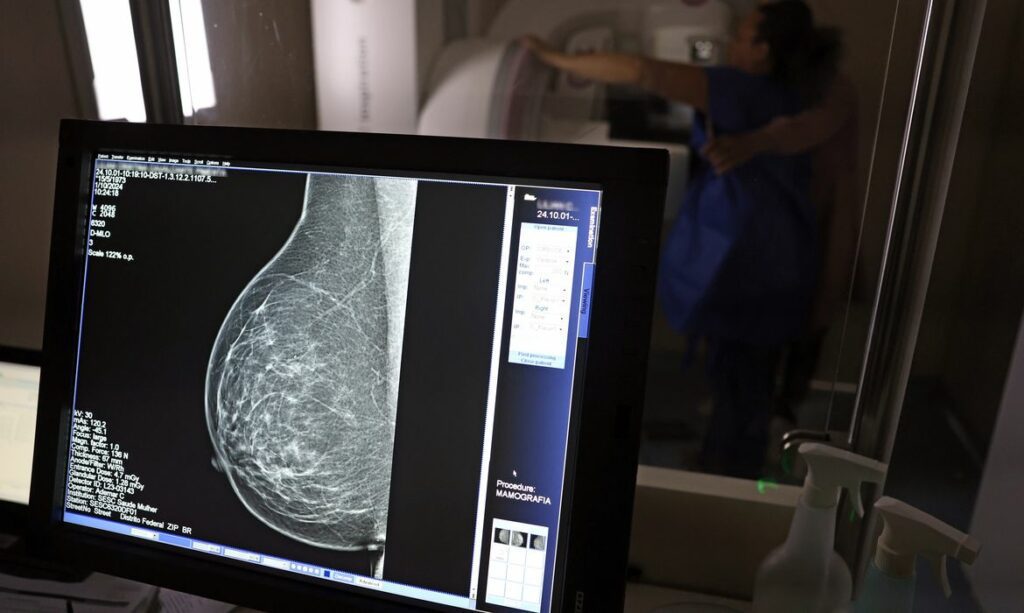

O câncer de mama, uma doença que anualmente afeta milhares de mulheres no Brasil, traz consigo não apenas desafios de saúde, mas também significativas implicações financeiras e sociais. O Instituto Nacional de Câncer (Inca) projeta um alarmante total de 73.610 novos casos para 2025, solidificando sua posição como o tipo de câncer que mais vitimiza mulheres no país. Neste cenário complexo, as pacientes em tratamento possuem uma série de direitos previdenciários e financeiros que se mostram fundamentais para garantir amparo e dignidade durante o período desafiador da recuperação. Estes incluem auxílio por incapacidade temporária, aposentadoria por incapacidade permanente e, em alguns casos, o Benefício de Prestação Continuada (BPC/LOAS), além de outras garantias essenciais.